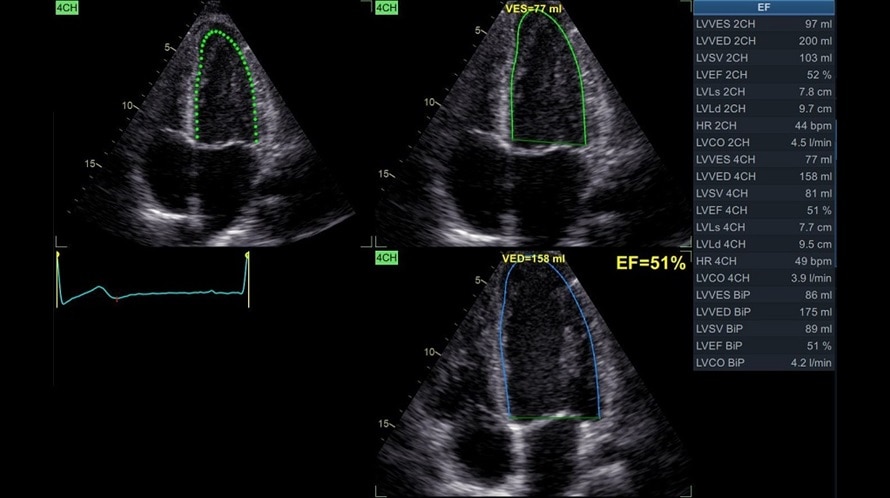

AutoEF

- Автоматически оценивает фракцию выброса левого желудочка на основе автоматического выделения зоны интереса по технологии спекл-трекинга.